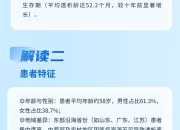

对于肾脏,大家可能是既熟悉又陌生,它是人体的重要器官,负责过滤血液中的废物、调节水分和电解质平衡、维持血压和产生红细胞等。慢性肾病(CKD)是全球重要的公共卫生问题,影响超过8.5亿人,数据表明,预计到2040年,慢性肾病将成为全球导致预期寿命缩短的第五大病因。慢性肾病早期往往没有明显症状,因此容易被忽视,当肾脏功能严重受损时,可能会导致肾衰竭,甚至需要透析或肾移植来维持生命。根据中国医师协会肾脏